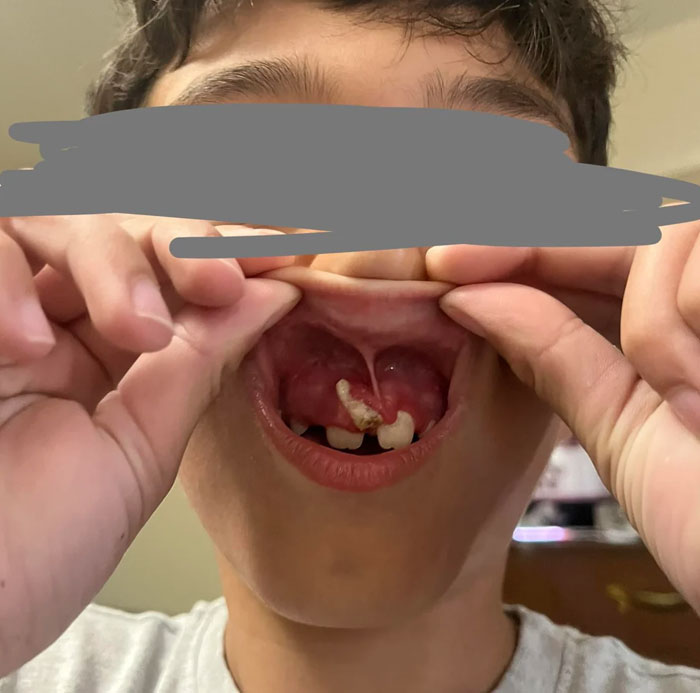

#43 My Sons Baby Tooth Won’t Fall Out. Dentist Won’t Remove It

Image credits: alysshaa19